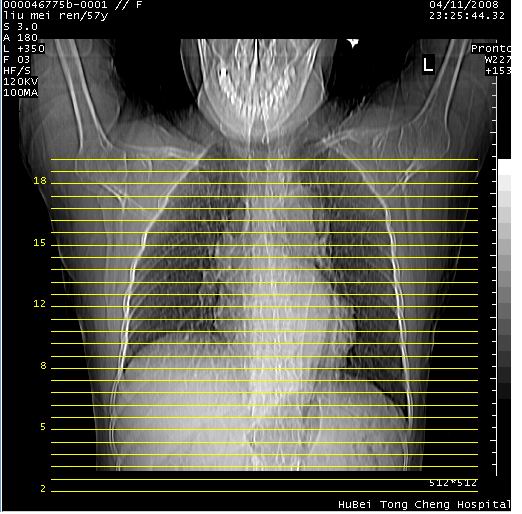

患者 女,57岁。因车祸受伤,其家属要求行“全身ct检查”。平素健康。

胸部ct轴位平扫(层厚10mm,螺距1.5,重建间隔10mm),图像如下: